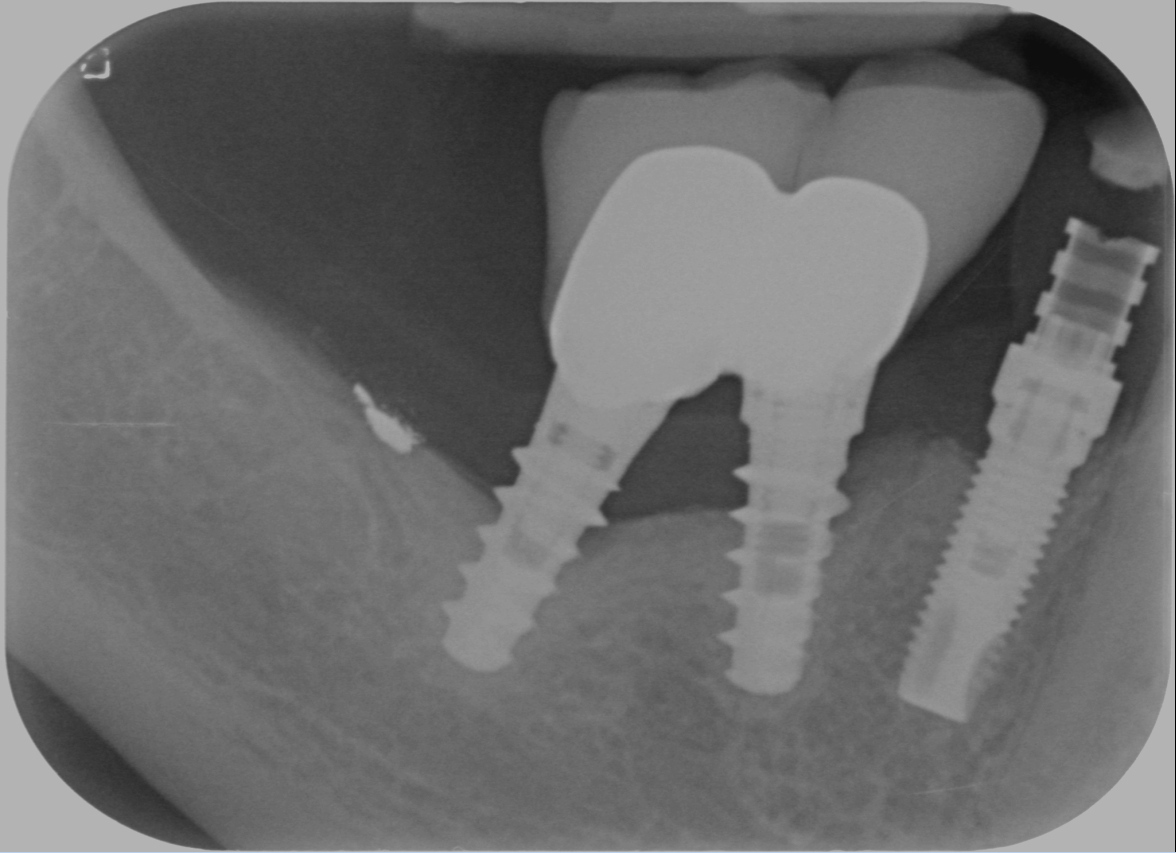

Questa è la situazione in cui mi si è presentato il caso:

Dopo la rimozione restavano solo 5 mm prima del nervo. Meno i due di sicurezza fanno 3 e, che io sappia, non ci sono impianti da 3 e anche ci fossero non li userei per trattare un pregresso fallimento!